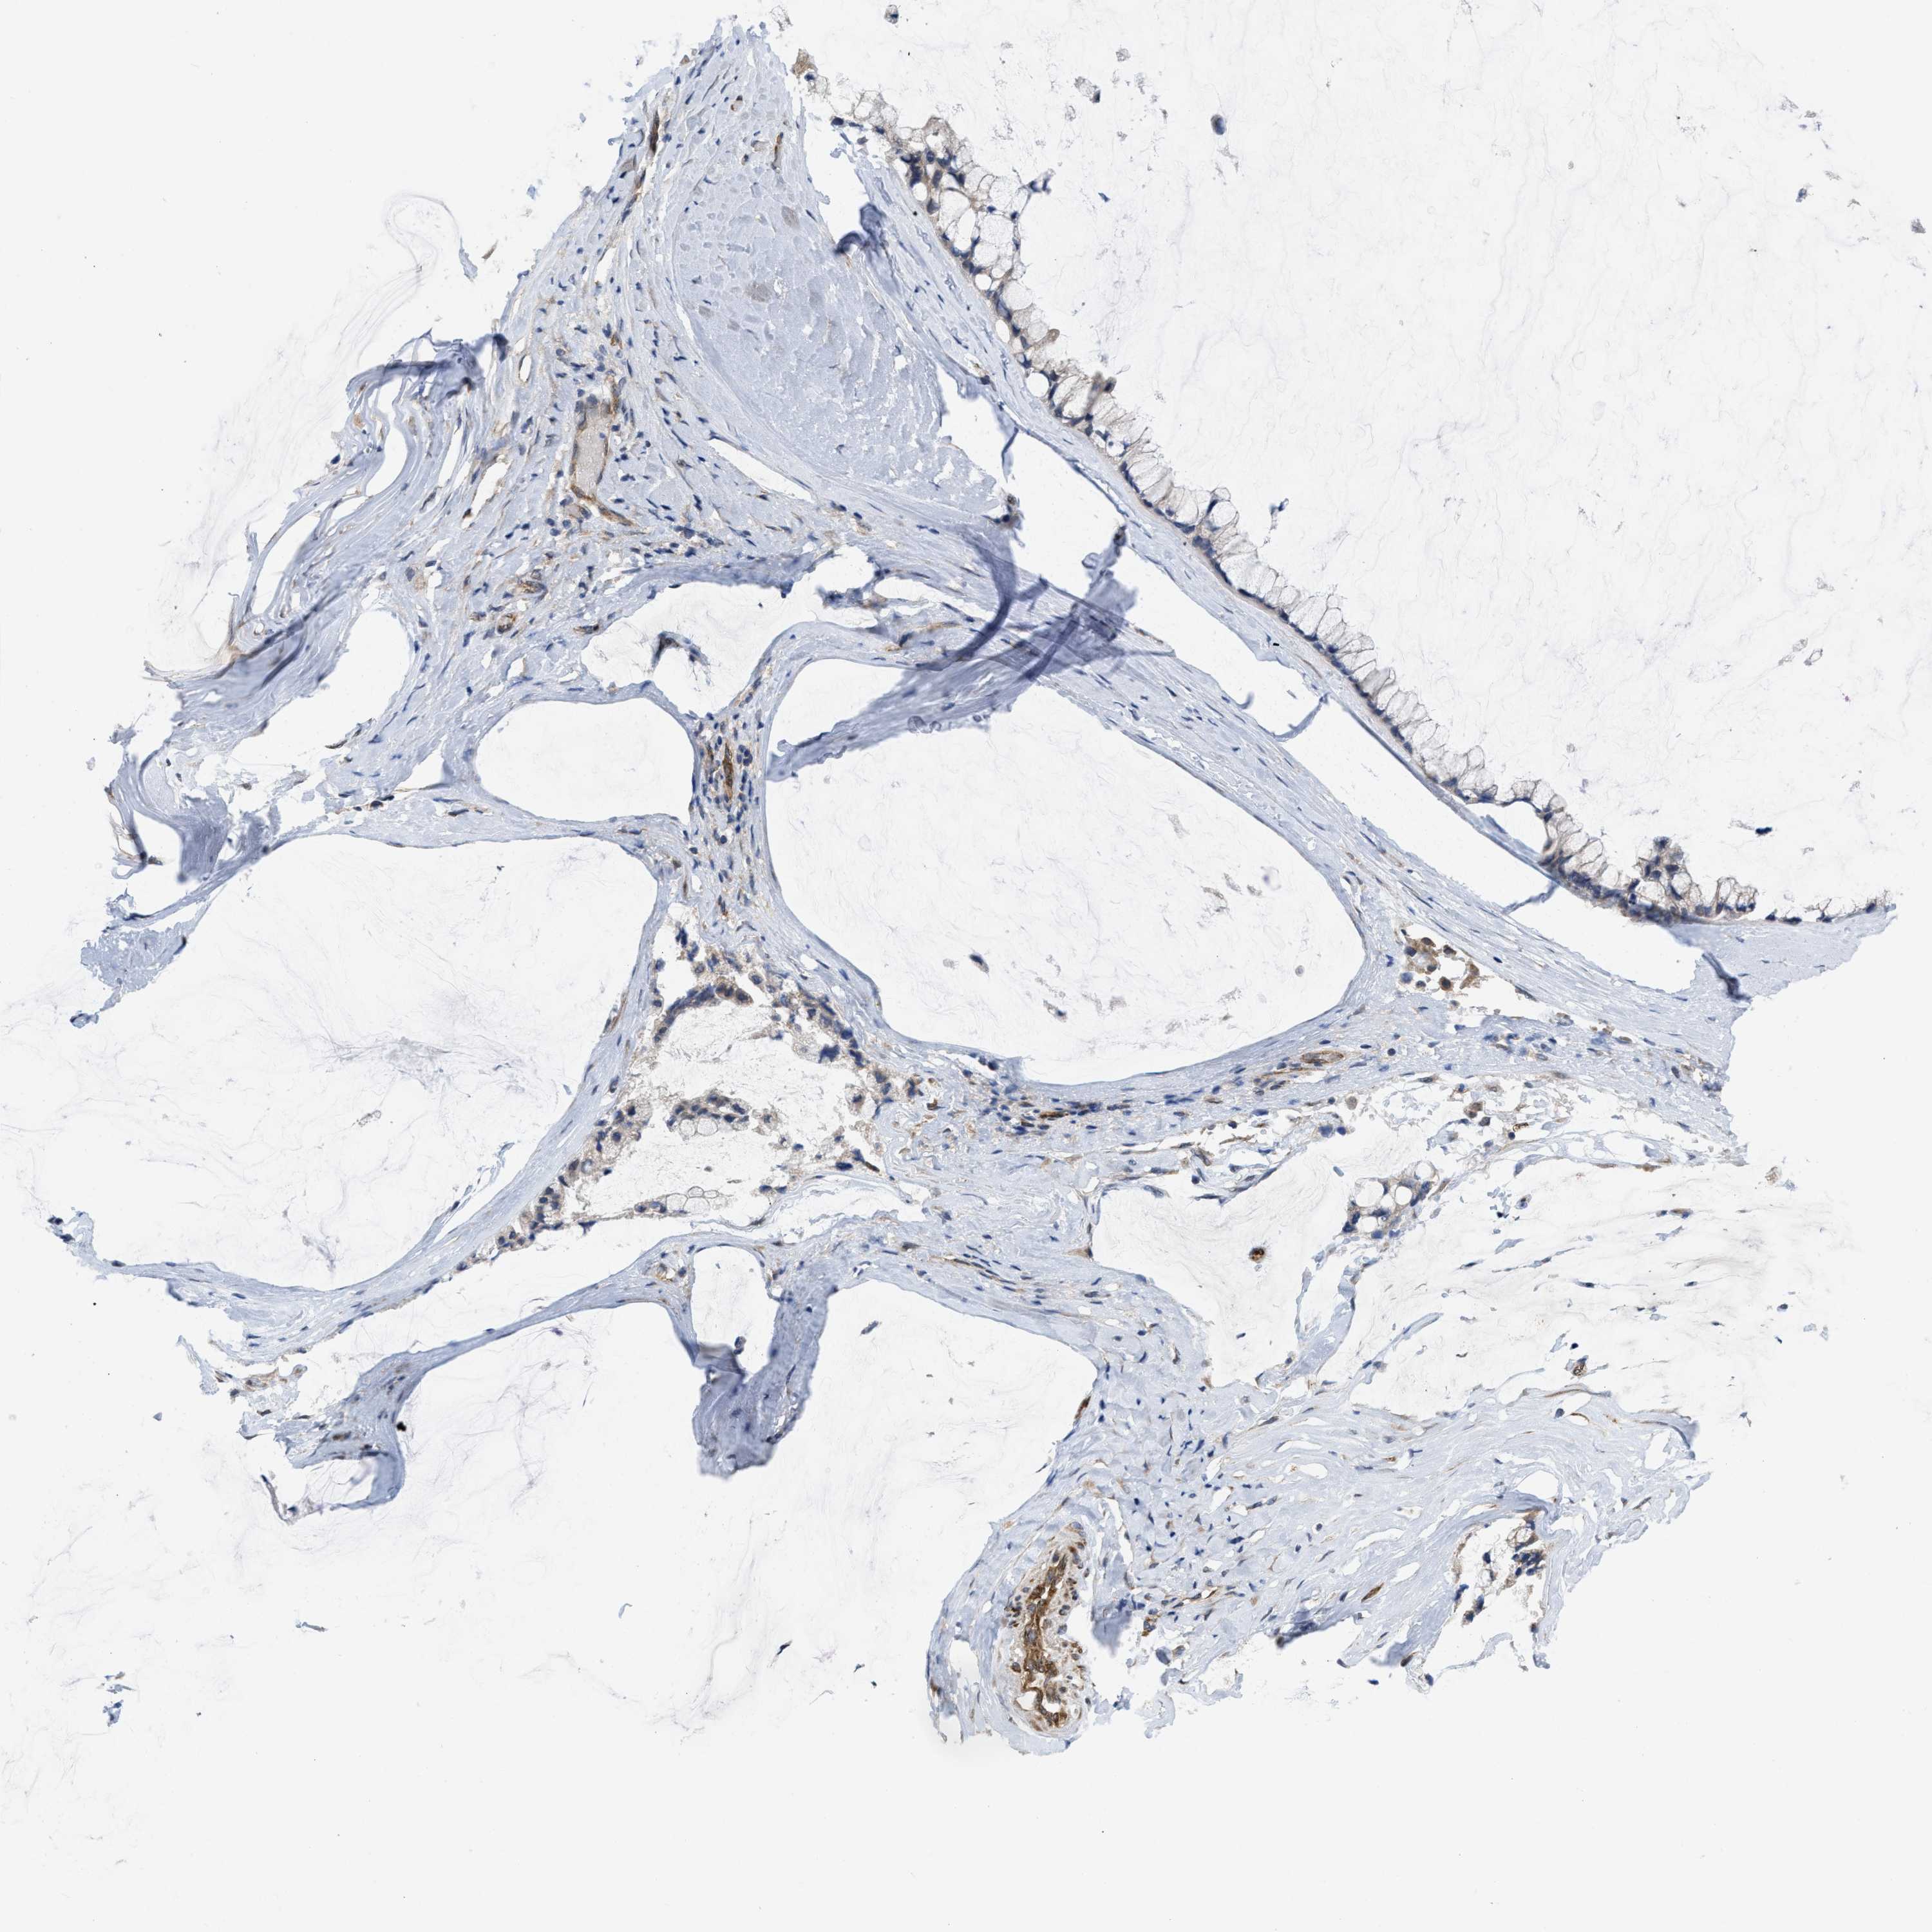

OVARIAN CANCER - Protein expressioni

A mouse-over function shows sample information and annotation data. Click on an image to view it in a full screen mode. Samples can be filtered based on level of antibody staining by selecting one or several of the following categories: high, medium, low and not detected. The assay and annotation is described here.

Note that samples used for immunohistochemistry by the Human Protein Atlas do not correspond to samples in the TCGA dataset.

Antibody stainingi

Antibody staining in the annotated cell types in the current human tissue is reported as not detected, low, medium, or high, based on conventional immunohistochemistry profiling in selected tissues. This score is based on the combination of the staining intensity and fraction of stained cells.

Each image is clickable and will lead to virtual microscopy that enables deeper exploration of all samples and also displays staining intensity scores, fraction scores and subcellular localization as well as patient and tissue information for each sample.

Antibody HPA019460

Staining

High

Medium

Low

Not detected

Intensity

Strong

Moderate

Weak

Negative

Quantity

>75%

75%-25%

<25%

None

Location

Nuclear

Cytoplasmic/membranous

Cytoplasmic/membranous,nuclear

Cystadenocarcinoma, serous, NOS

Carcinoma, endometroid

Cystadenocarcinoma, mucinous, NOS

Carcinoma, NOS